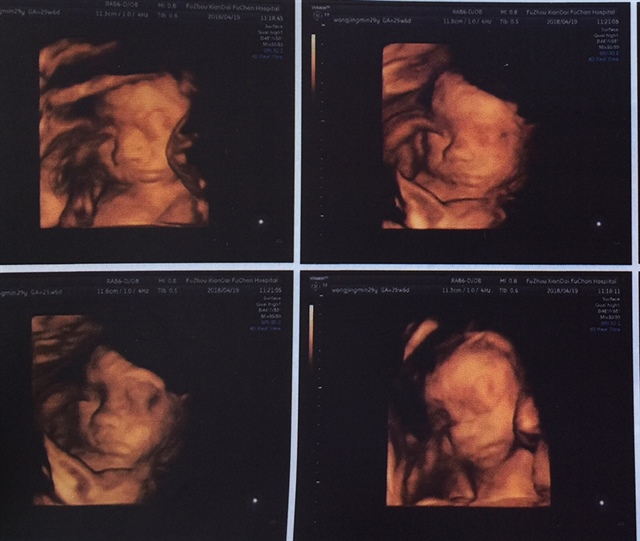

最后一张图看不懂